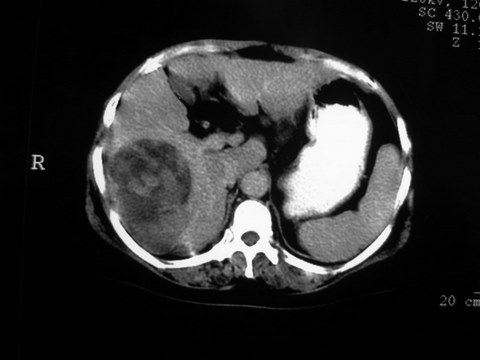

患者 女 51岁 两天前感觉上腹疼,无明显诱因,b超示肝右叶囊实性占位,边缘清楚,其内回声不均匀,ct增强如图,大家看看是什么 ,病人一年前及两月前b超检查只是提示胆囊炎

外院术后,证实肝癌合并出血

特点:1,病灶发展迅速,(2月前正常)[br] 2,囊实性,且并边界清晰光滑,呈右后叶赘生性。囊性区无强化,实性部分较多轻度强化,边界欠清。考虑囊腺癌或囊腺瘤。

增强扫描好像都没有强化的,不管灶周还是灶中心,支持考虑包虫病,别不除外肝囊内内出血,那些一块一块的为血凝块

出病理 中分化肝细胞癌合并出血